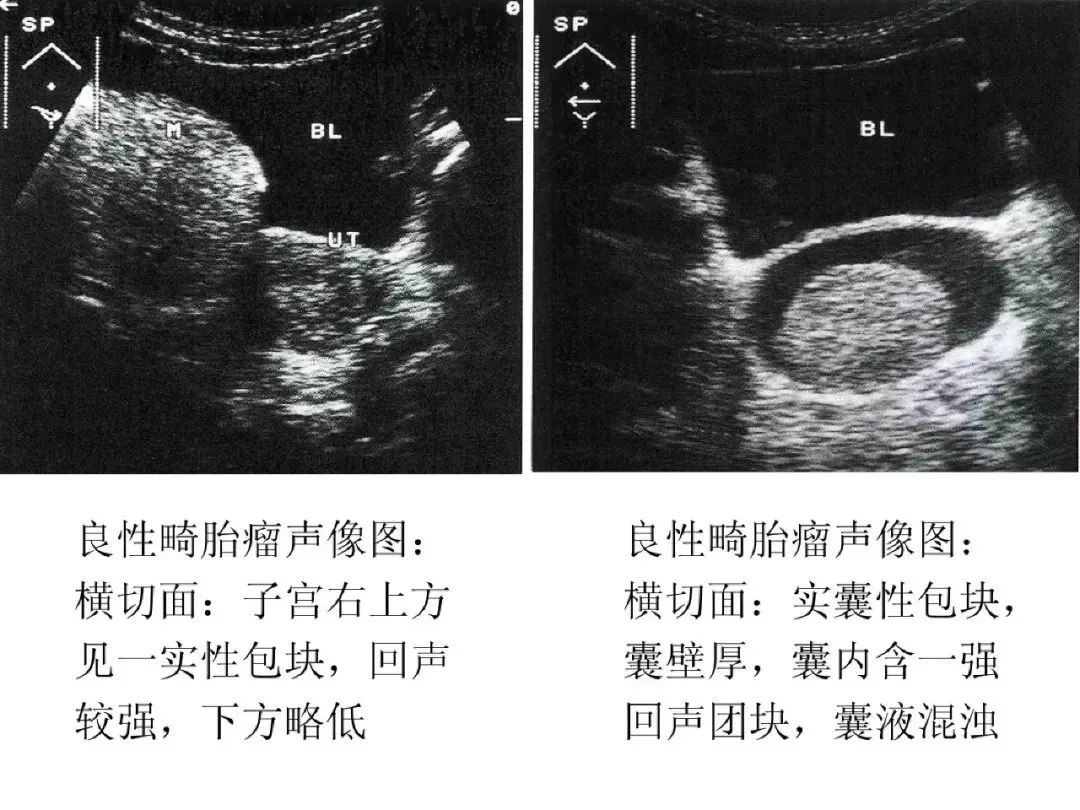

良性畸胎瘤与恶性畸胎瘤

●良性畸胎瘤超声特点:圆形或椭圆形,多为单侧;壁厚,清晰或不清;囊内显示飘浮光点,如面团征、发团征、脂液分层征;内可显示强回声光团、光带。

●恶性畸胎瘤:卵巢恶性畸胎瘤为恶性生殖细胞肿瘤,含有未成熟或胚胎性混合组织,多发生于年轻女性,占卵巢肿瘤的0.2%。

●声像图特征:肿瘤较大,呈圆形、椭圆形或欠规则;瘤壁厚;内部回声较复杂,可出现脂液分层,强回声光团或低回声实性区;内部血流较丰富。